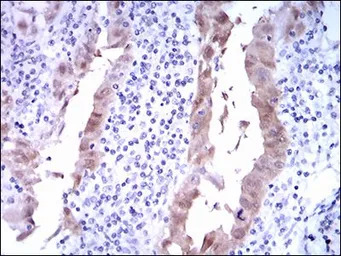

IHC-P analysis of lung cancer tissue using GTX60663 CDKN2A / p16INK4a antibody [1D7D2].